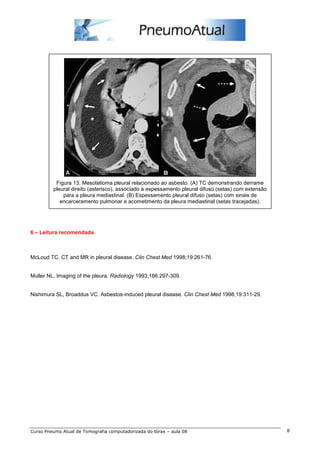

Figura 13. Mesotelioma pleural relacionado ao asbesto. (A) TC demonstrando derrame

pleural direito (asterisco), associado a espessamento pleural difuso (setas) com extensão

para a pleura mediastinal. (B) Espessamento pleural difuso (setas) com sinais de

encarceramento pulmonar e acometimento da pleura mediastinal (setas tracejadas).